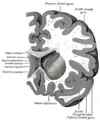

Transverse Cut of Brain (Horizontal Section), basal ganglia is blue

Together with the putamen, the caudate forms the dorsal striatum, which is considered a single functional structure; anatomically, it is separated by a large white matter tract, the internal capsule, so it is sometimes also referred to as two structures: the medial dorsal striatum (the caudate) and the lateral dorsal striatum (the putamen). In this vein, the two are functionally distinct not as a result of structural differences, but merely due to the topographical distribution of function.

The caudate nuclei are located near the center of the brain, sitting astride the thalamus. There is a caudate nucleus within each hemisphere of the brain. Individually, they resemble a C-shape structure with a wider "head" (caput in Latin) at the front, tapering to a "body" (corpus) and a "tail" (cauda). Sometimes a part of the caudate nucleus is referred to as the "knee" (genu).[7] The caudate head receives its blood supply from the lenticulostriate artery while the tail of the caudate receives its blood supply from the anterior choroidal artery.[8]